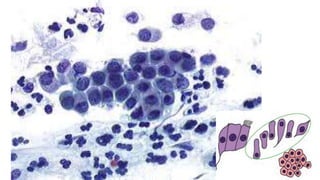

Citoplasma relativamente abundante, delicado,

semitransparente, que cora fracamente em azul, às vezes com

vacúolos.

Os núcleos são redondos ou ovais, com alguma variação do

tamanho, cromatina finamente granular exibindo cromocentros

ou nucléolo.

Quando as células são vistas lateralmente, assumem a forma

colunar alta característica, com núcleo oval, localizado na

região basal. Nessa perspectiva, quando em conjuntos,

constituem os arranjos conhecidos como “fila”, ou “paliçada”.

Quando as células são vistas de frente, elas se agrupam em

conjuntos monoestratificados, perdem a sua forma colunar e

apresentam, às vezes, bordas citoplasmáticas bem definidas,

lembrando um “favo de mel”. Os núcleos arredondados

mostram polaridade conservada (a distância entre os núcleos

é relativamente constante, não ocorrendo sobreposição

nuclear).